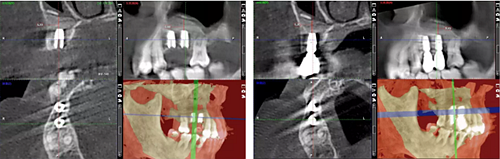

術后14個月

從組織學上看,植入早期并未出現大量炎性細胞浸潤,表明材料的組織相容性較好并能有效地發(fā)揮支架作用。β-TCP同時具有大孔兼微孔結構,微孔結構對于材料的生物可吸收性具有重要影響,有利于組織的滲入,形成局部酸性環(huán)境,促進材料的降解;而大孔結構則有利于發(fā)揮材料的骨傳導性,較大的表面積可促進材料在體內的降解。同時材料的微孔結構也有利于骨組織的長入,對材料的早期固定和骨缺損修復提供了有益的物理結構。

隨著間充質細胞的長入,β-TCP逐漸被分割包圍,有血管形成和吞噬細胞浸潤,β-TCP開始降解,為新生骨的形成進一步提供空間,最終修復骨缺損。